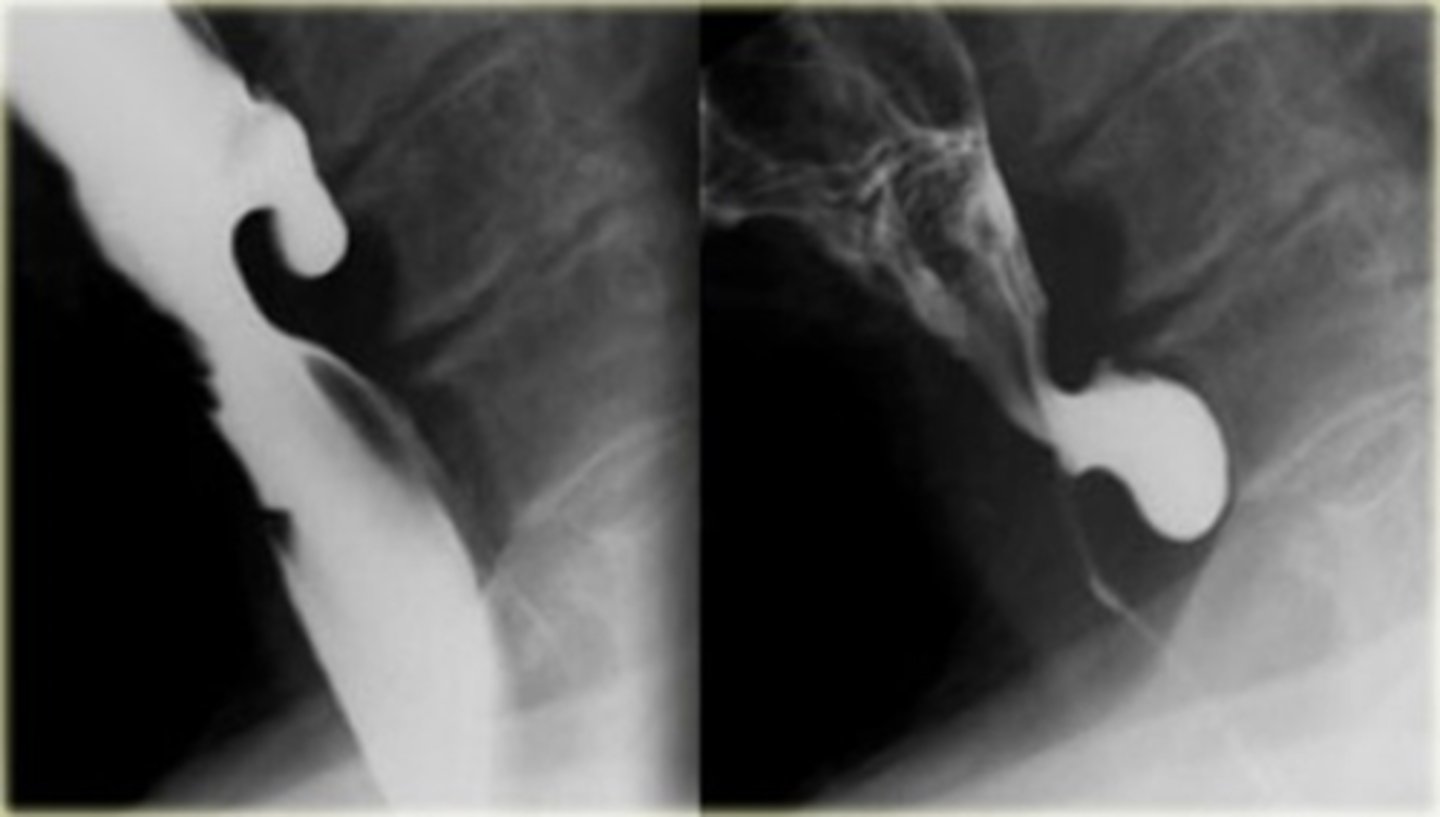

Upper left esophageal carcinoma

Lower left barrett's esophagus

Upper right hiatal hernia with schatzki's ring

THICK WHITE ARROW: Schatzki's ring

THING WHITE ARROW: stricture